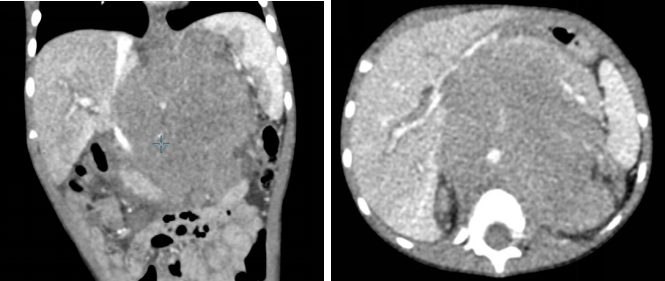

腹部(CT平扫+增强)(2024.03.01):

腹膜后中线区见实性肿块,范围90.3*90.9*99.5mm。

腹部CT增强(2024.05.31):

左侧肾上腺区及腹主动脉旁见软组织肿块影,较大处位于左肾上腺区,范围49.3*24.5*28.7mm。

4个疗程后疗效评估:部分缓解(PR)。